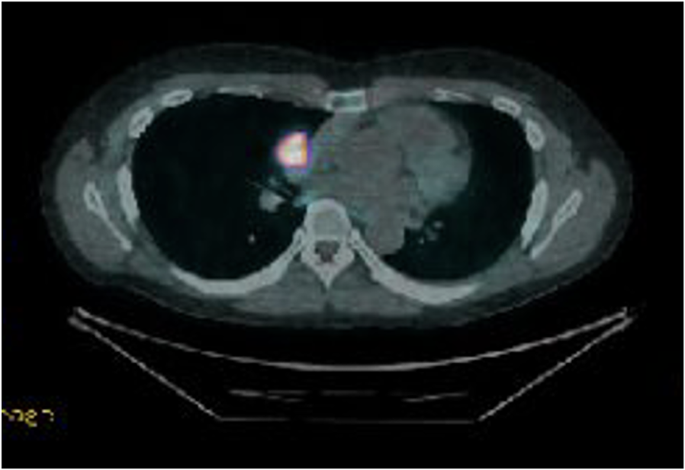

DOTATE PET demonstrating significant uptake in carcinoid tumour

A DOTATATE PET CT scan showed recurrence of his thymic carcinoid at the level of the groove between the right main pulmonary artery and right atrium, growing very close to the phrenic nerve. It was advised for him to undergo complete excision of the lesion requiring a joint approach from cardiac and thoracic surgeons. The patient subsequently underwent a median sternotomy, removal of recurrent mediastinal tumour invading the pericardium and wedge resection of the lung, lymph node sampling.